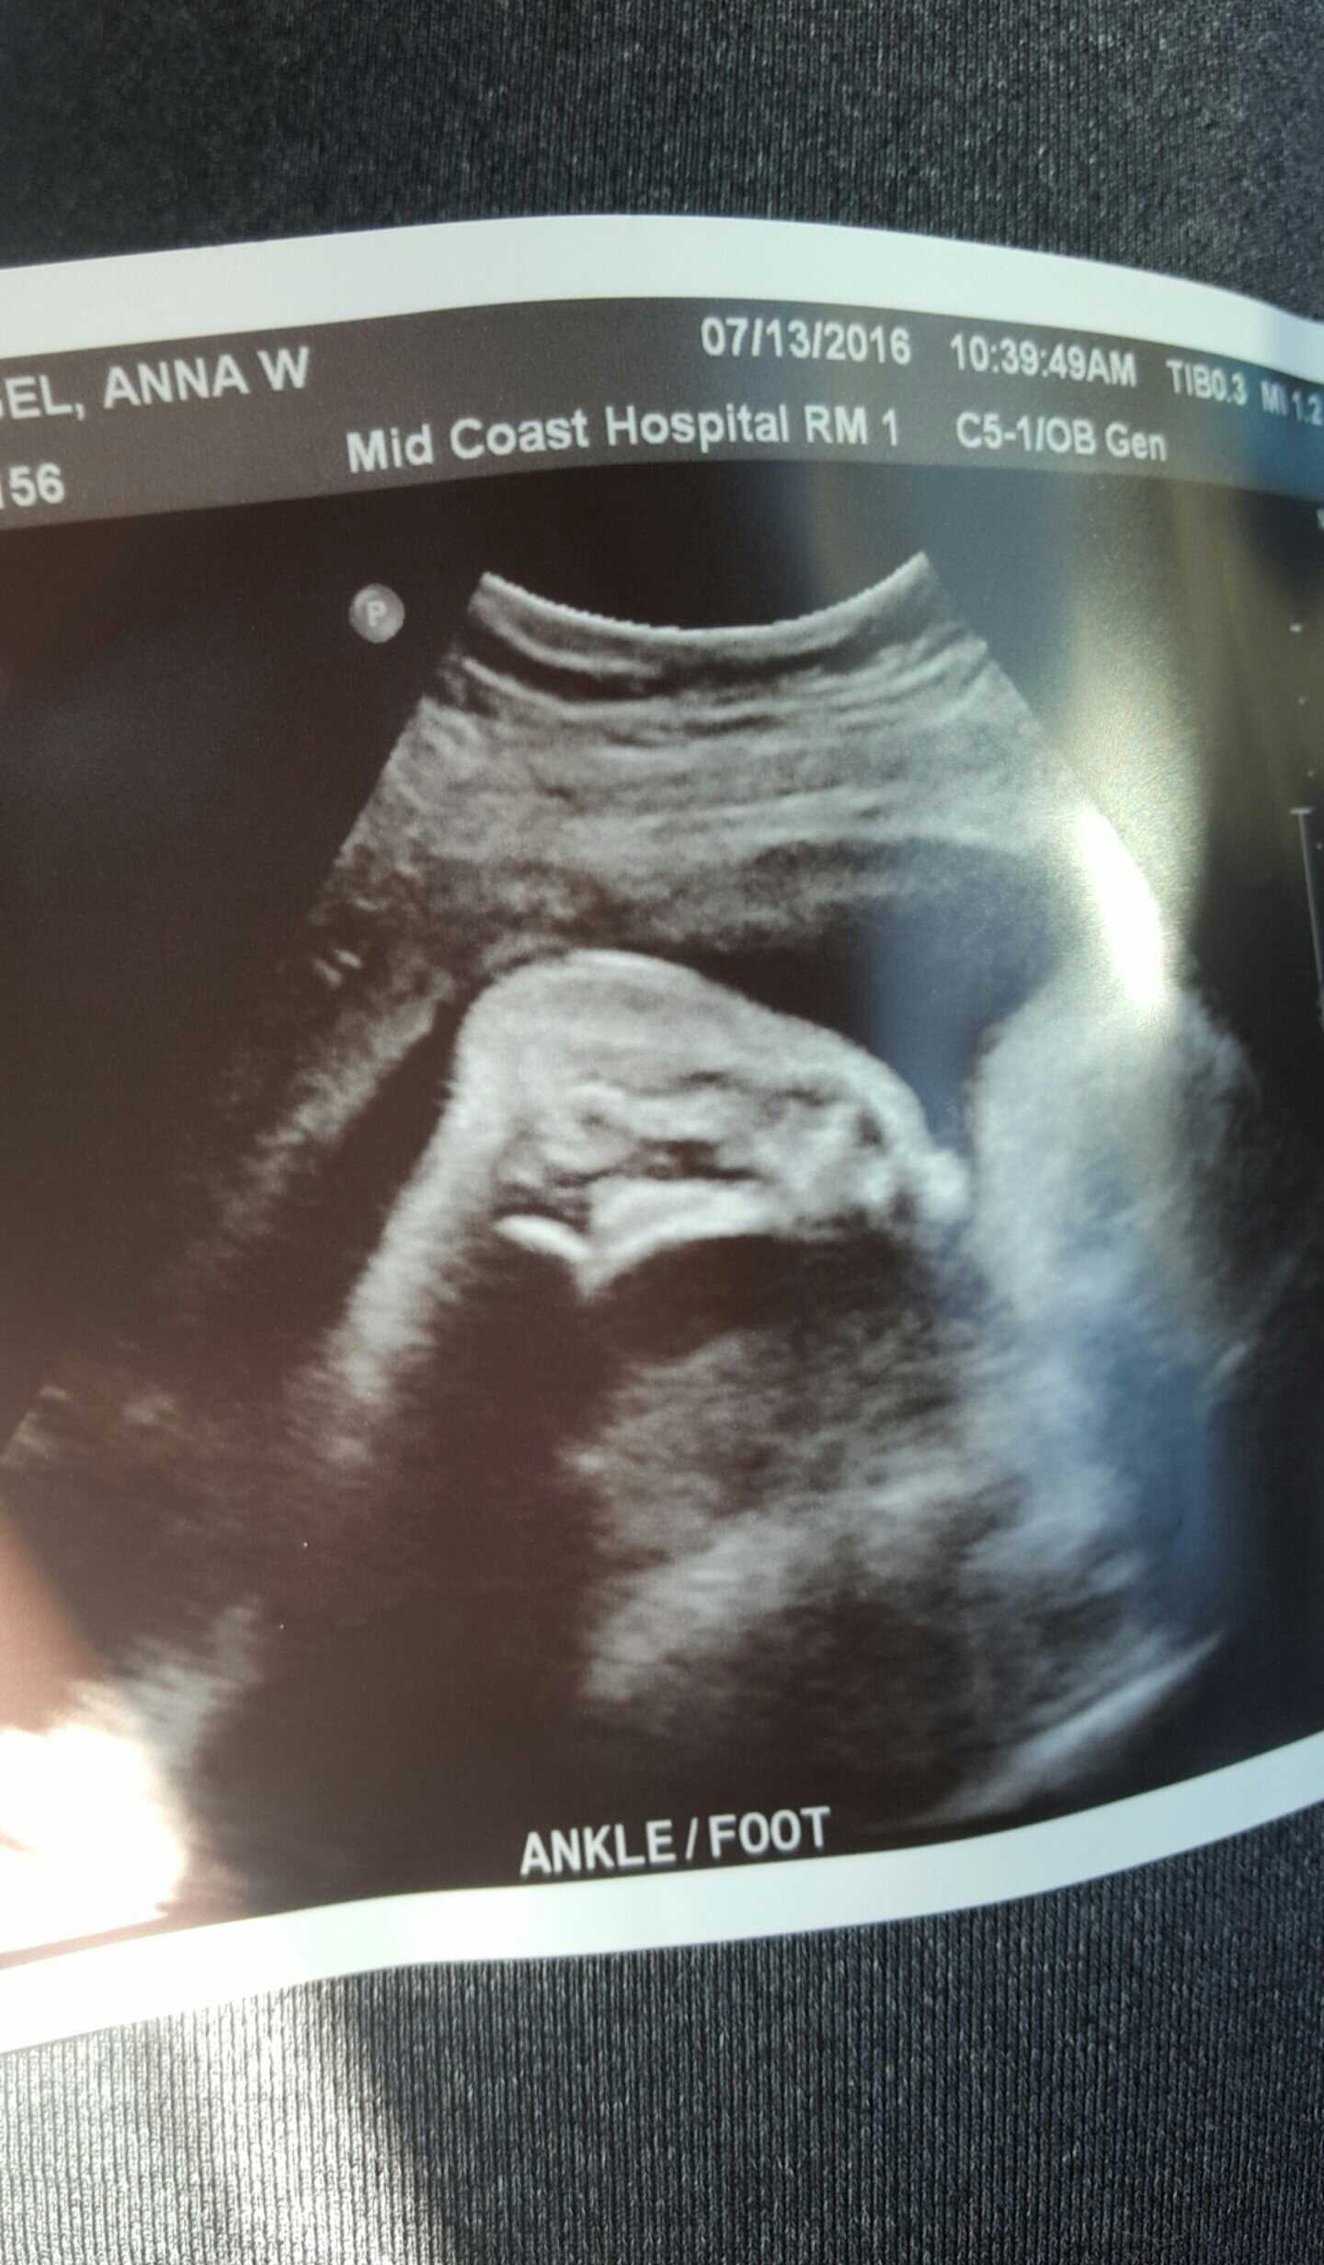

Wake up, Anna.